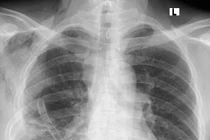

Tức nặng ngực không ngờ u trung thất đè ép tim, phổi | Báo Tri thức và Cuộc sống - TIN TỨC PHỔ BIẾN KIẾN THỨC 24HU trung thất thường tiến triển một cách âm thầm, lặng lẽ nên khó phát hiện sớm. Khi xuất hiện triệu chứng u đã chèn ép tim, phổi, mạch máu lớn hoặc di căn... u trung thất,khối u,Tức nặng ngực,u trung thất khổng lồ,tim,phổi